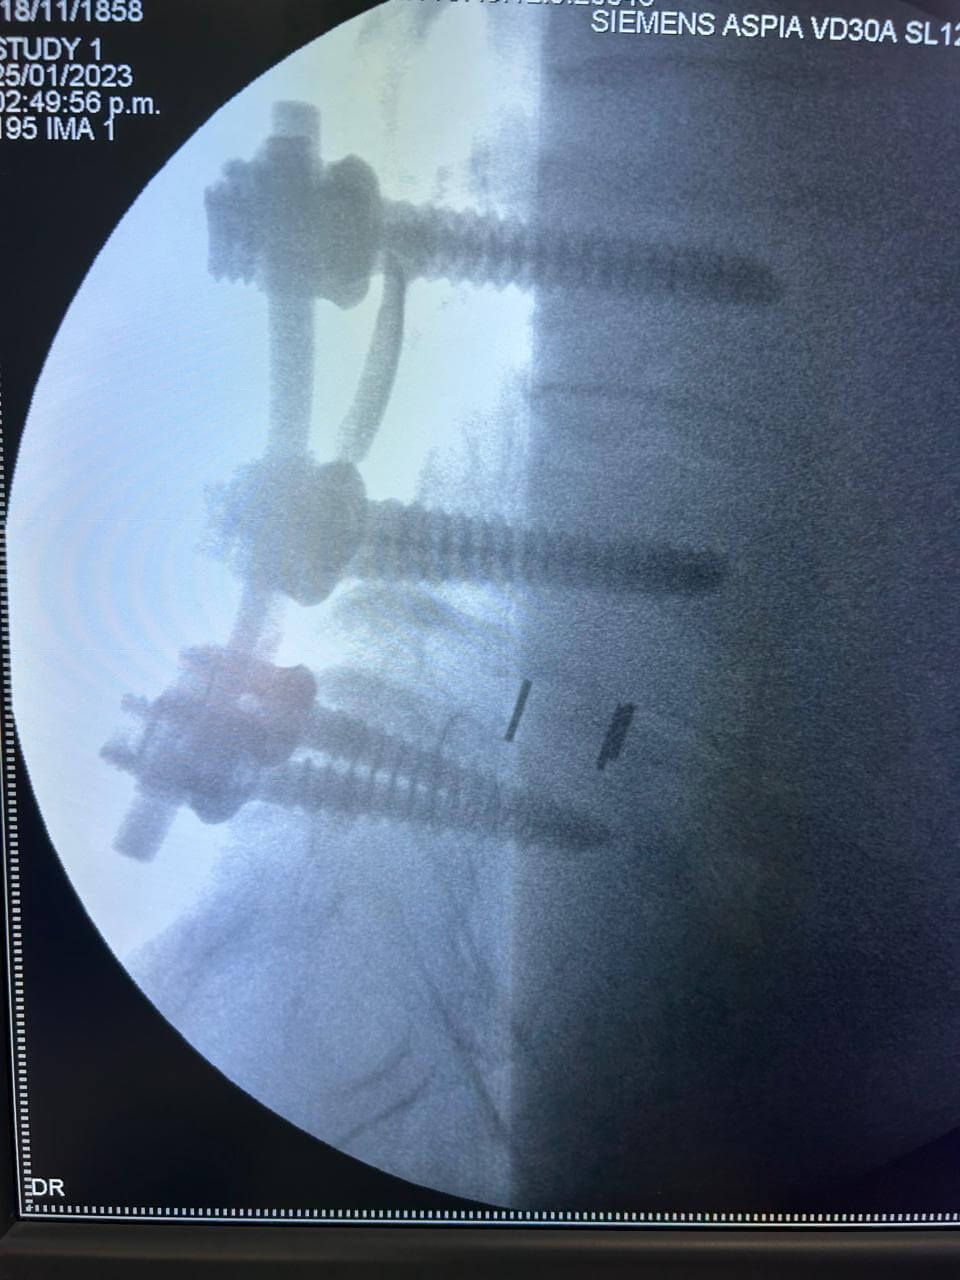

Cirugía de mínima invasión de columna vertebral

Realiza cirugías endoscópicas mínimamente invasivas de columna.

Cirugía de Columna

Realiza cirugía habitual y endoscópica mínimamente invasiva de columna vertebral.